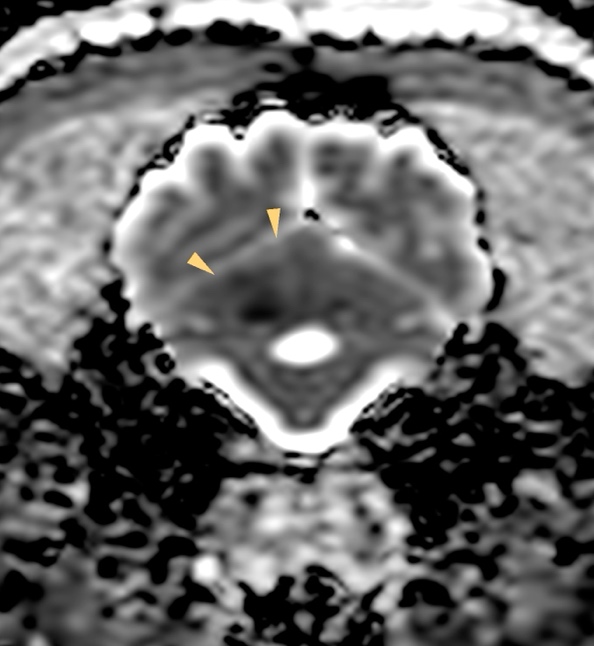

MRI所見

小脳右前小脳動脈領域にT2WI/FLAIR:高信号、DWI:高信号、ADC:一部低信号(部分的な拡散抑制を示唆)

→急性期小脳梗塞を強く疑う所見

この症例もやっぱり小脳中位核を含んでいます、瞳孔不同(右眼散瞳)があったに違いない!!

【MR画像】横断像 ADC-map

【MR画像】横断像 ADC-map